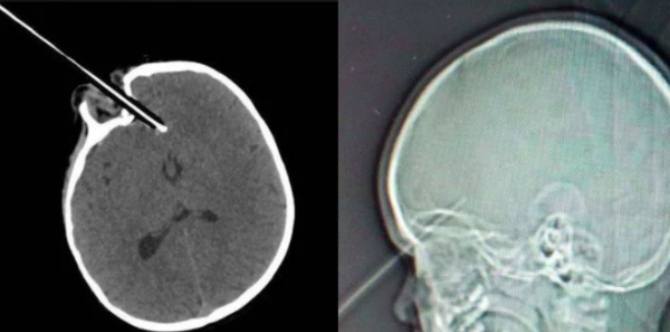

This is when she tripped on a stair gate while holding a pencil. As confirmed by an X-ray (photos above), the sharpened pencil stabbed her in the eye and then penetrated all the way into 1 1/2 inches of the front of her brain.

Toddler’s eye stabbed by pencil in freak accident: The pencil pierced through the toddler’s eye and lodged itself into her brain, just missing vital arteries. | Images from: Medicare Video